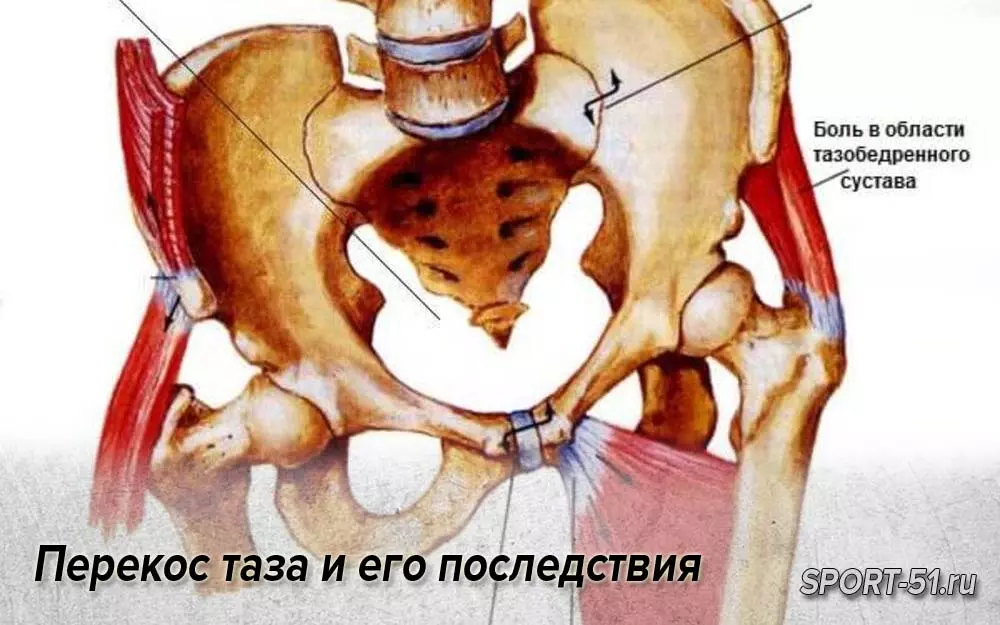

Анатомия и упражнения: Перекос таза и мышцы бедра